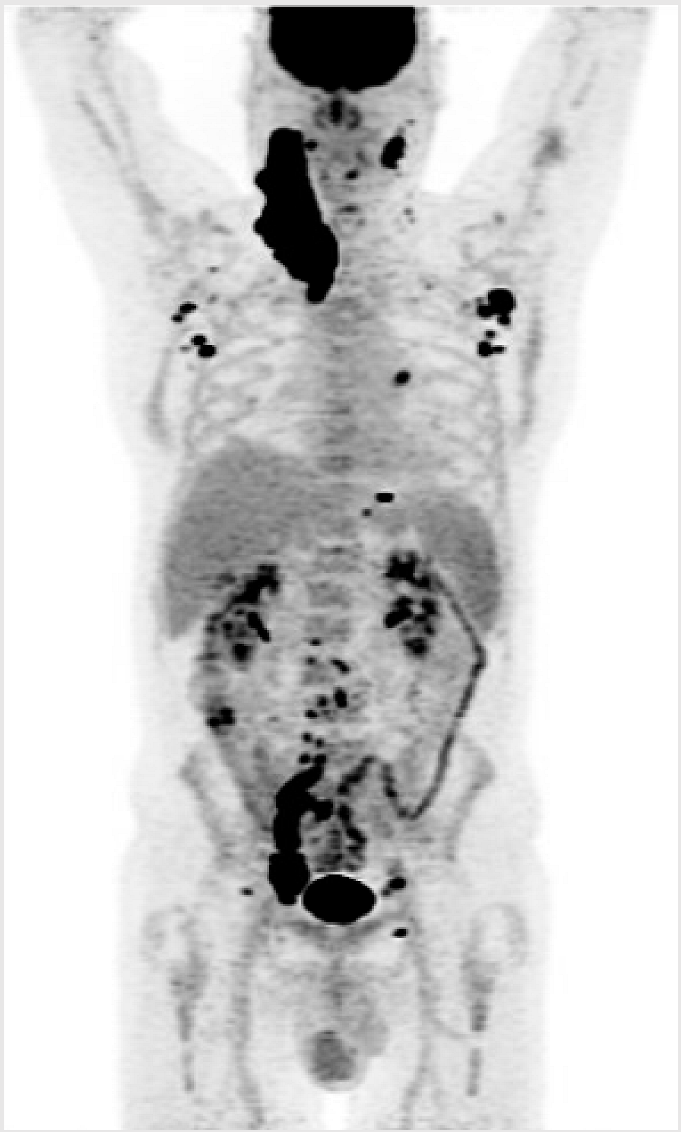

3.3. Illustrative Case 3

Key Clinical Features

| ![]() ![]() |

ASCT—autologous stem cell therapy; BMT—bone marrow transplant; BR—bendamustine–rituximab; CAD—coronary artery disease; CR—complete response; DLBCL—diffuse large B-cell lymphoma; ECOG—Eastern Cooperative Oncology Group; HDT—high-dose therapy; HTN—hypertension; IPI—international prognostic index; LDH—lactate dehydrogenase; MI—myocardial infarction; PET—positron emission tomography; PR—partial response; PS—performance status; R-CHOP—rituximab–cyclophosphamide–doxorubicin–vincristine–prednisone; R-GDP—rituximab–gemcitabine–cisplatin–dexamethasone; ULN—upper limit of normal.

Key Points for Illustrative Case 3

- CAR-T cell therapy requires a coordinated process involving significant contributions by the patient and healthcare team [14,17]. CAR-T cell therapy requires, at minimum, the following: an initial consultation; leukapheresis; and a lymphodepleting therapy and infusion with the necessity of the patient staying in proximity to the CAR-T cell center to complete a total of one month after infusion. The vast majority of patients are hospitalized during the initial 2 weeks after CAR-T infusion. It is also recommended that patients have a caregiver accompany them during the CAR-T cell therapy process;

- The administration of BsAbs involves frequent visits for therapy, which contrasts with the one-time administration of the CAR-T cell product. Individual preferences will likely influence patient decision-making;

- The length of time away from home was the driving factor in this patient’s preference for BsAbs. Despite the frequency of administration of BsAb therapy, he preferred to travel back and forth for the shorter visits;

- For many patients, the necessity of travel and an extended stay near the CAR-T cell center is a meaningful barrier. The requirement to travel for treatment involves personal, familial, financial, and professional considerations. Patients’ geographic distance to treatment centers is a major limitation for many patients, with those residing 2–4 h away being 40% less likely to access CAR-T cell therapy [35]. The mapping of CAR-T cell therapy administered in the province of Quebec illustrated this unfortunate reality [36];

- Some remote centers may initiate the ramp-up of BsAbs in a regional hospital or cancer center, with later cycles administered closer to home in an infusion clinic;

- The incidence of CRS occurrence from cycle 2 onwards is very low (less than 5%), and its severity is mild (typically grade 1 or 2) [1,3]. Moreover, the occurrence of CRS from cycle 2 onwards is often observed in patients who experience more severe or prolonged CRS during cycle 1, making it more predictable. The incidence and severity of neurotoxicity with BsAbs is also low, further supporting the feasibility of administration at local centers with regional oversight;

- Having a caregiver present during the ramp-up of BsAbs is recommended but not absolutely necessary, as long as patients are reliable and compliant. If there are particular concerns about a patient’s condition and reliability, their monitoring period in the hospital could be extended;

- For patients who do not want to or cannot travel for CAR-T cell therapy, BsAbs may represent a valuable treatment option. However, the duration of follow-up from BsAb clinical trials remains insufficient to assess the curative potential of this approach.